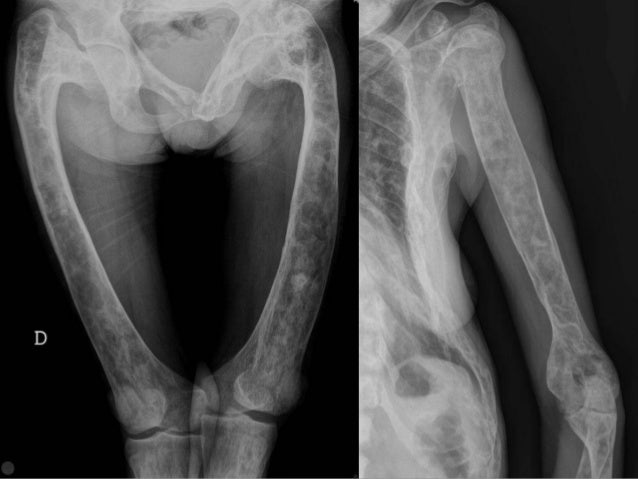

La displasia fibrosa è in medicina, una malattia ossea che si manifesta con uno sviluppo anormale dell'osso. Si sviluppa soprattutto nella costa.

Esistono le forme monostotica, dove viene coinvolto un osso solo e la forma poliostotica che invece si manifesta in più ossa, in tal caso si può osservare la sindrome di McCune-Albright.

La displasia raramente mostra sintomi risultando per la maggior parte asintomatico. Solo nelle forme più gravi si assiste durante la fase dello sviluppo ad una possibile zoppia, per via dell'accorciamento delle ossa, fino ad arrivare alla cosiddetta “bastone da pastore”.